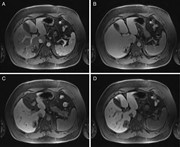

Concurrent hepatic hemangioma and solitary fibrous tumor: diagnosis and management

Michael Kueht and others

Journal of Surgical Case Reports, Volume 2015, Issue 7, July 2015, rjv089, https://doi.org/10.1093/jscr/rjv089